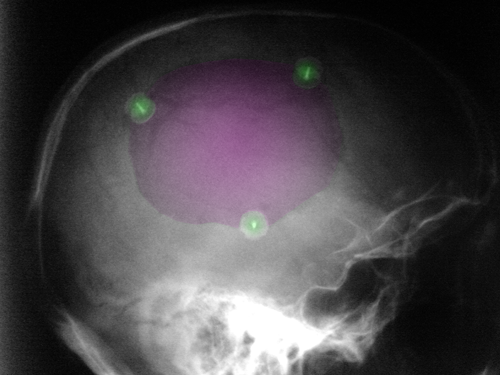

Περιγραφή Η επέμβαση γίνεται υπό γενική αναισθησία. Κατά κανόνα χρησιμοποιείται η υπάρχουσα δερματική τομή της κρανιεκτομίας. Ο δερματικός κρημνός αποκολλάται από την υποκείμενη μήνιγγα έως τις παρυφές του οστικού ελλείμματος. Η αποκατάσταση γίνεται με την τοποθέτηση ή του οστού που είχε αφαιρεθεί στην κρανιεκτομία ή με συνθετικό εμφύτευμα. Στην πρώτη περίπτωση πρέπει να έχει προηγηθεί φύλαξη του οστού σε βαθειά ψύξη και κατόπιν απολύμανση με ακτινοβολία. Σπανιότερα μετά την κρανιεκτομία γίνεται φύλαξη του αφαιρεθέντος οστικού τεμαχίου με μετεμφύτευση στο υποδόριο του κοιλιακού τοιχώματος. Εάν το οστικό τεμάχιο δεν έχει φυλαχθεί για πρακτικούς λόγους ή δεν μπορούσε να επαναχρησιμοποιηθεί λόγω καταστροφής του (από την προηγηθείσα κάκωση) τότε χρησιμοποιείται συνθετικό εμφύτευμα. Το συνθετικό εμφύτευμα μπορεί να πλασθεί από πολυμερές ακρυλικό (PMMA) διεγχειρητικά ή να τοποθετηθεί προκατασκευασμένο εμφύτευμα από πολυμερές το οποίο μπορεί να μορφοποιηθεί σε μέγεθος, σχήμα και καμπυλότητα. Υπάρχει επίσης και η δυνατότητα τοποθέτησης προκατασκευασμένου - με τη βοήθεια τρισδιάστατης ανασύνθεσης της αξονικής τομογραφίας του ασθενούς - συνθετικού μοσχεύματος το οποίο τοποθετείται ήδη μορφοποιημένο. Ο κρημνός (οστικός ή συνθετικός) στερεώνεται με στηρικτικές πλάκες ή clip από τιτάνιο ή τεχνητό οστό ή ράμματα. |

Κρανιοπλαστική (μώβ). 3 στηρικτικά κλιπ τιτανίου με πράσινο. |